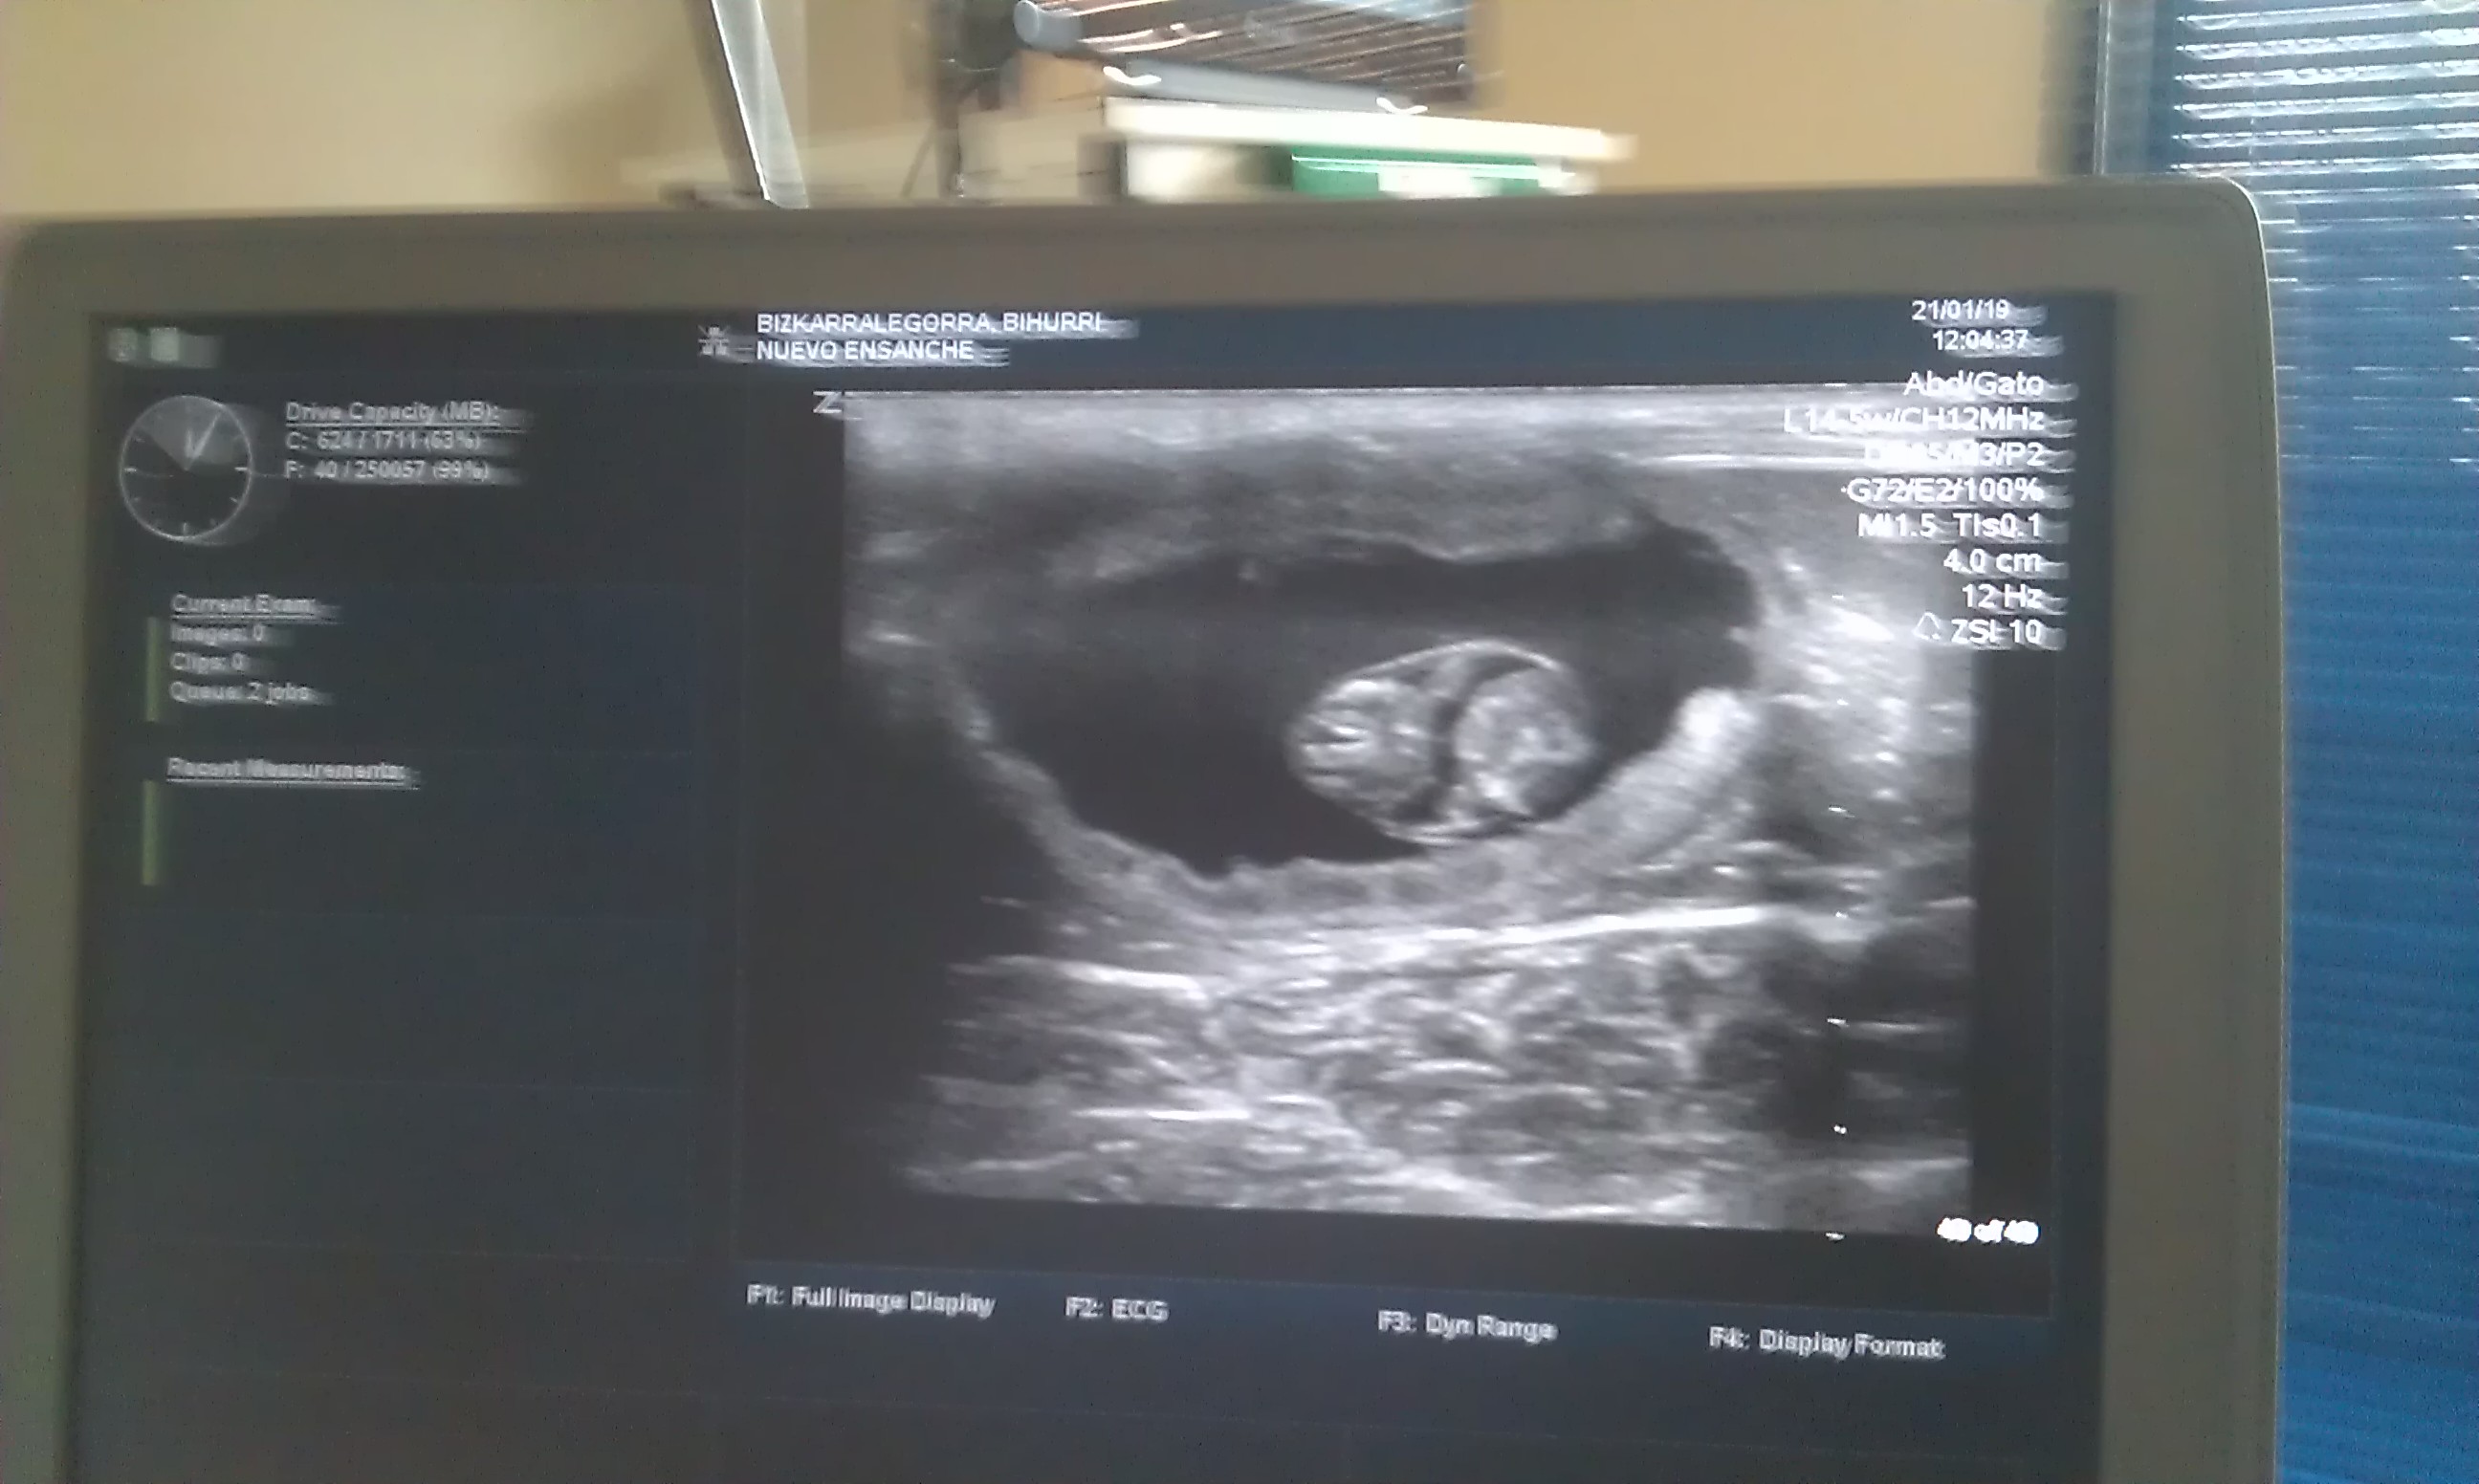

Día de gestación 23

L. 21-1-2019

Las ecografías confirman que 4 crías están en camino.

Bihurri (2d), cría-9c